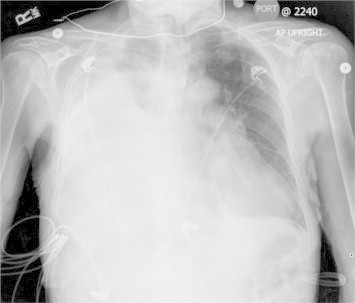

The patient was admitted and treated for presumed healthcare associated pneumonia with vancomycin and ceftazidime, diuresis, supplementary oxygen and continued peritoneal dialysis. The next day, her clinical condition worsened, with oxygen saturation dropping to 91% on 6 L/minute by nasal canula. A repeat chest radiograph (Fig. 3) demonstrated worsening of the right pleural effusion. Emergent ultrasound-guided thoracocentesis was performed, and 3.8 L of colorless pleural fluid was drained. The patient had significant clinical improvement, with oxygen saturation increasing to 97% on 2 L/minute.

Fig. 3.

AP chest radiograph 12 hours after admission.